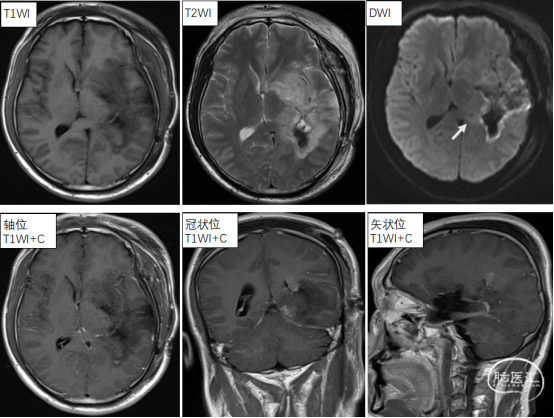

今年3月,63岁的李女士(化名)来到树兰(济南)医院就诊。彼时,她被胶质母细胞瘤反复折磨,身体极度虚弱。因化疗导致头发大把脱落,行走艰难,只能扶着墙勉强挪步。胶质母细胞瘤作为恶性程度最高、侵袭性最强的脑肿瘤之一,严重威胁着她的生命健康。

李女士入院后,神经肿瘤科陶荣杰主任迅速率领团队展开救治。团队运用液体活检技术,仅用72小时就精准锁定了MET基因异常扩增这一病灶关键。针对这一异常基因,团队采用新型靶向药阻断肿瘤细胞的生长信号传导通路,从源头遏制癌细胞的增殖与侵袭,为后续治疗争取到了宝贵时间。

经过三个月的治疗,李女士的肿瘤缩小超30%,原本无力的肢体逐渐恢复力量,生活基本能够自理。这一显著的治疗效果打破了胶质母细胞瘤“绝症”的固有认知,为众多患者带来了新的希望。